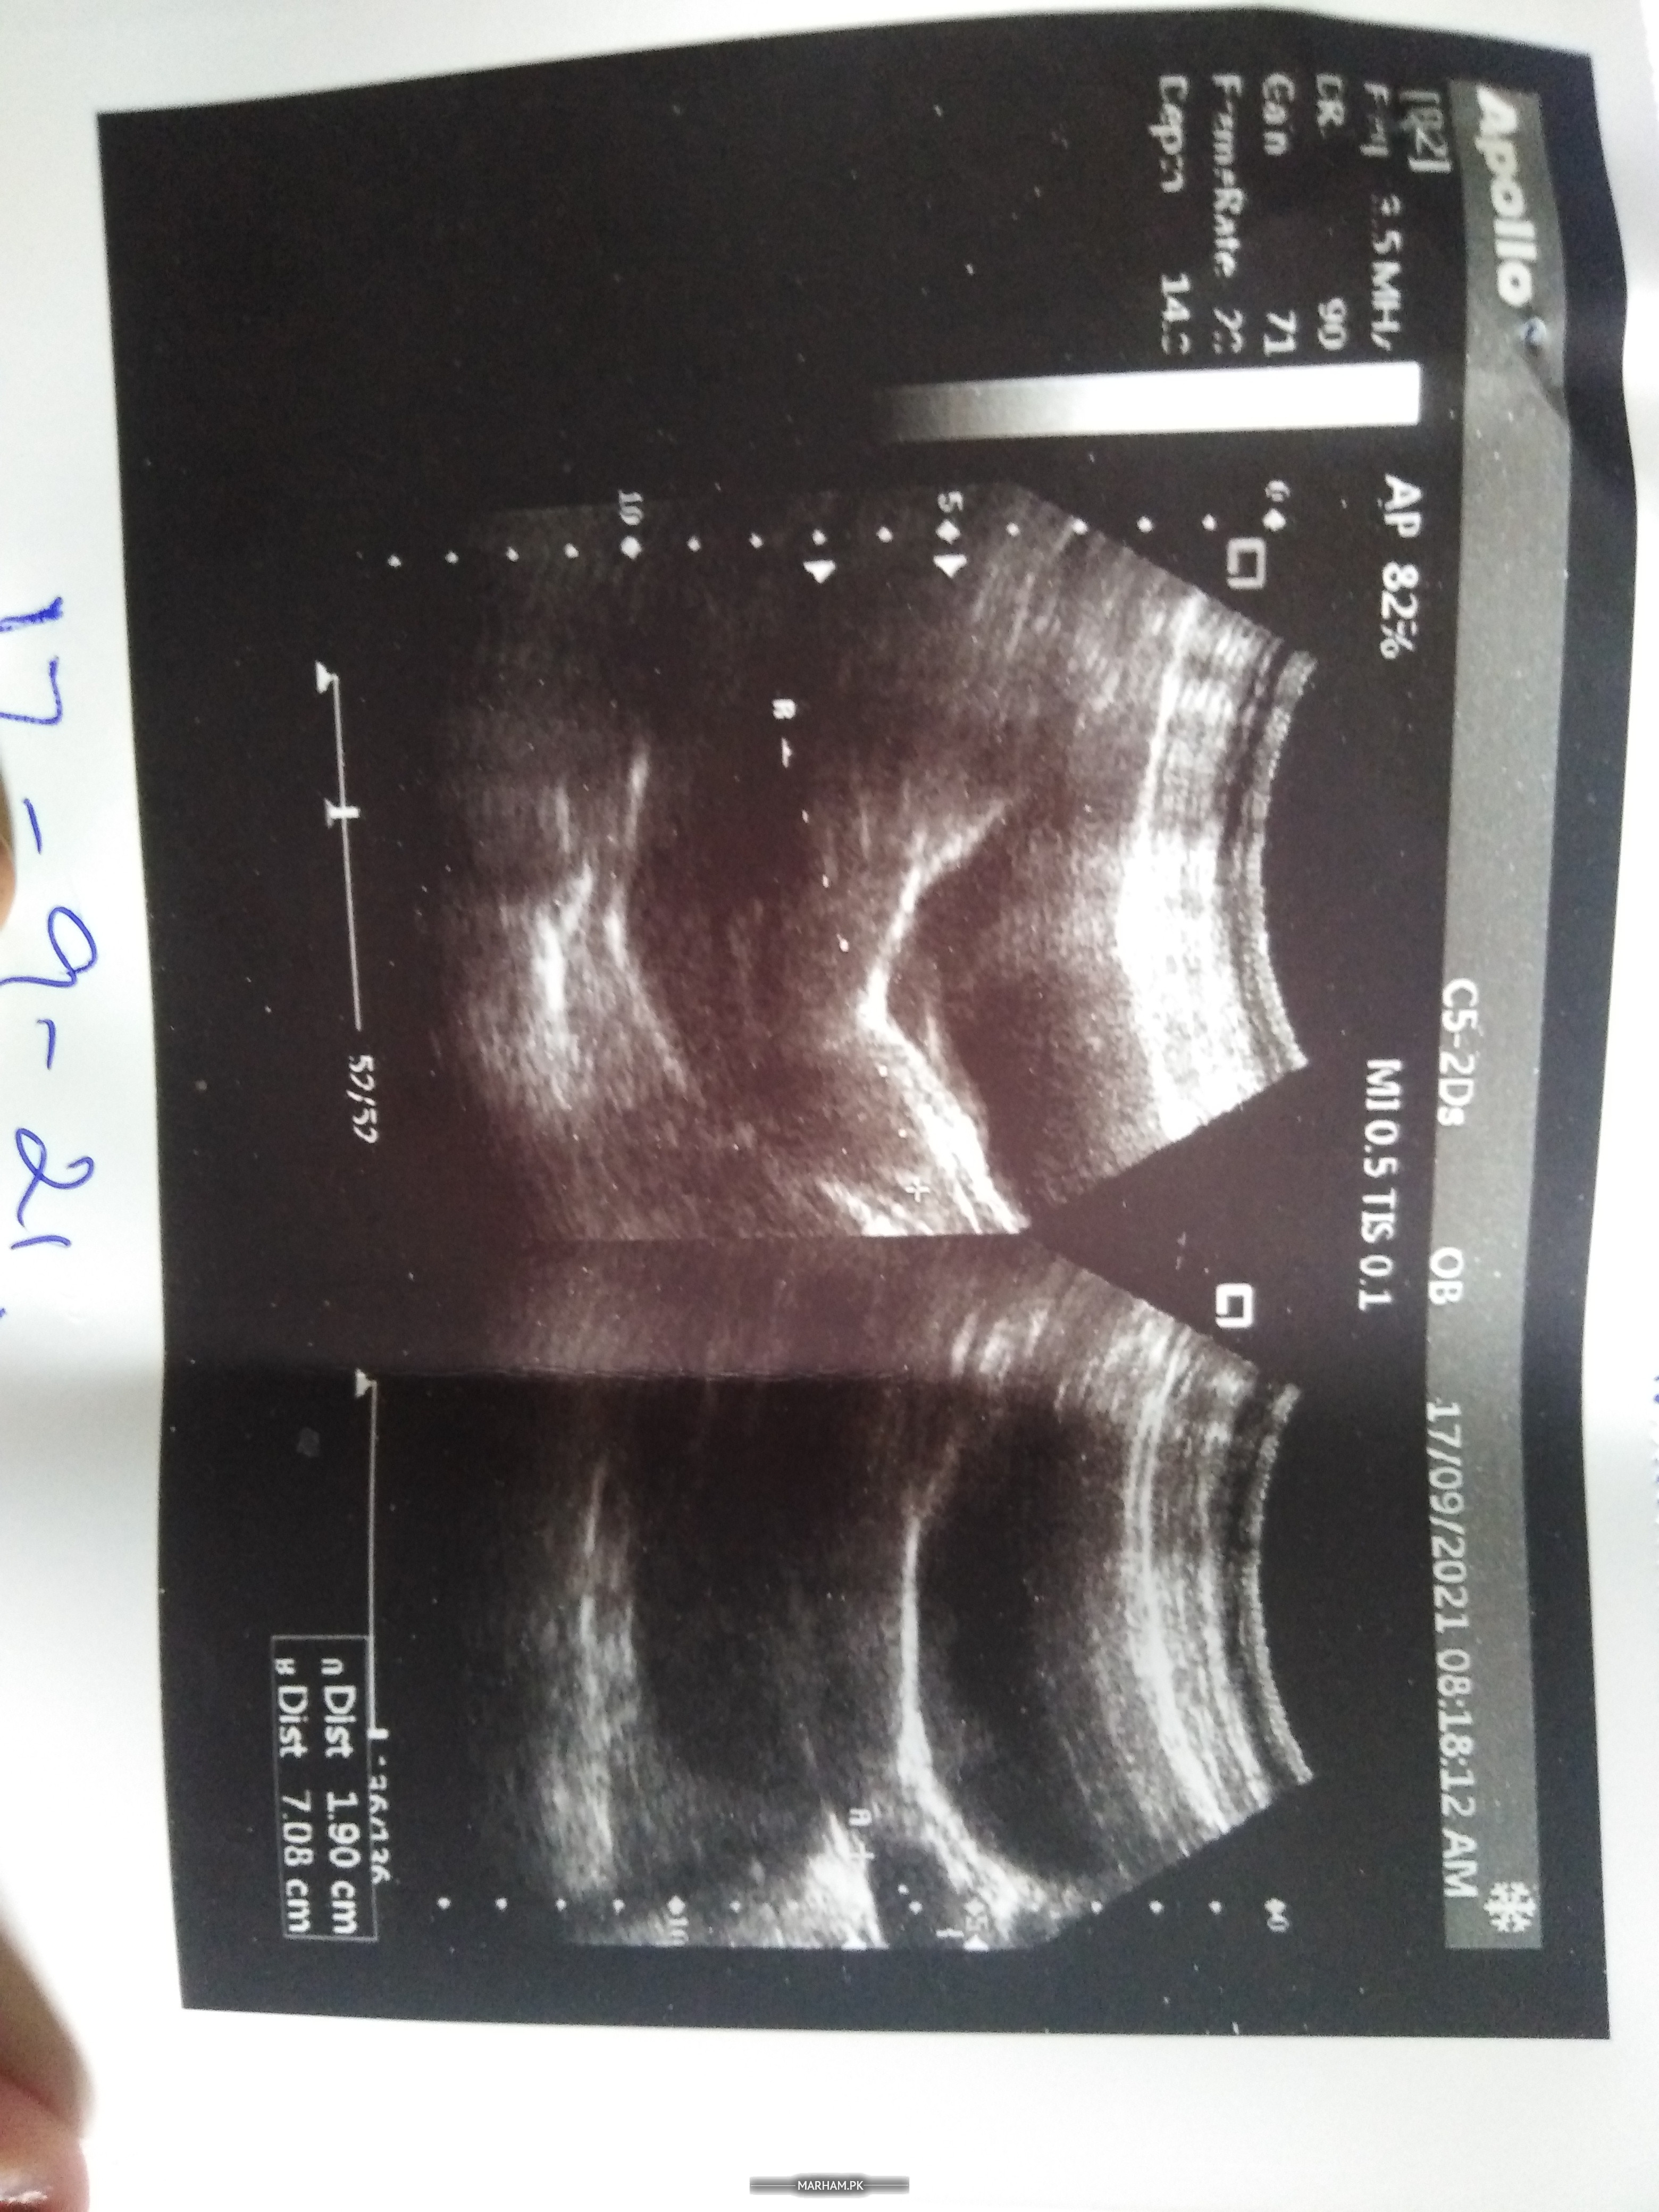

And this is an ultrasound.